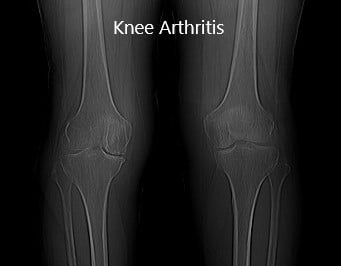

Imaging revealed severe bilateral Osteoarthritis of the knee. The patient was symptomatic mainly in the right knee, he was advised a custom total knee replacement. Risks, benefits and potential complications were all discussed with the patient in detail. He was highly motivated to get back to his baseline and opted for custom total arthroplasty.

Preoperative X-ray showing AP view of the bilateral knee joints